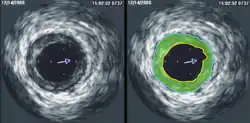

Ultrasonografia wewnątrzwieńcowa (ang. intracoronary ultrasound, ICUS) – inwazyjne badanie ultrasonograficzne, będące odmianą ultrasonografii wewnątrznaczyniowej (intravascular ultrasound, IVUS), umożliwiające zobrazowanie światła i ściany naczynia wieńcowego.

Badanie polega na wprowadzeniu do światła naczynia wieńcowego miniaturowej głowicy ultrasonograficznej (o średnicy 1-1,5 mm), emitującej ultradźwięki o częstotliwości 20 - 50 MHz.

W trakcie wycofywania cewnika ultrasonograficznego uzyskuje się sekwencję poprzecznych przekrojów naczynia, która dzięki technikom komputerowym zostaje przedstawiona jako trójwymiarowa rekonstrukcja obrazowanego naczynia.